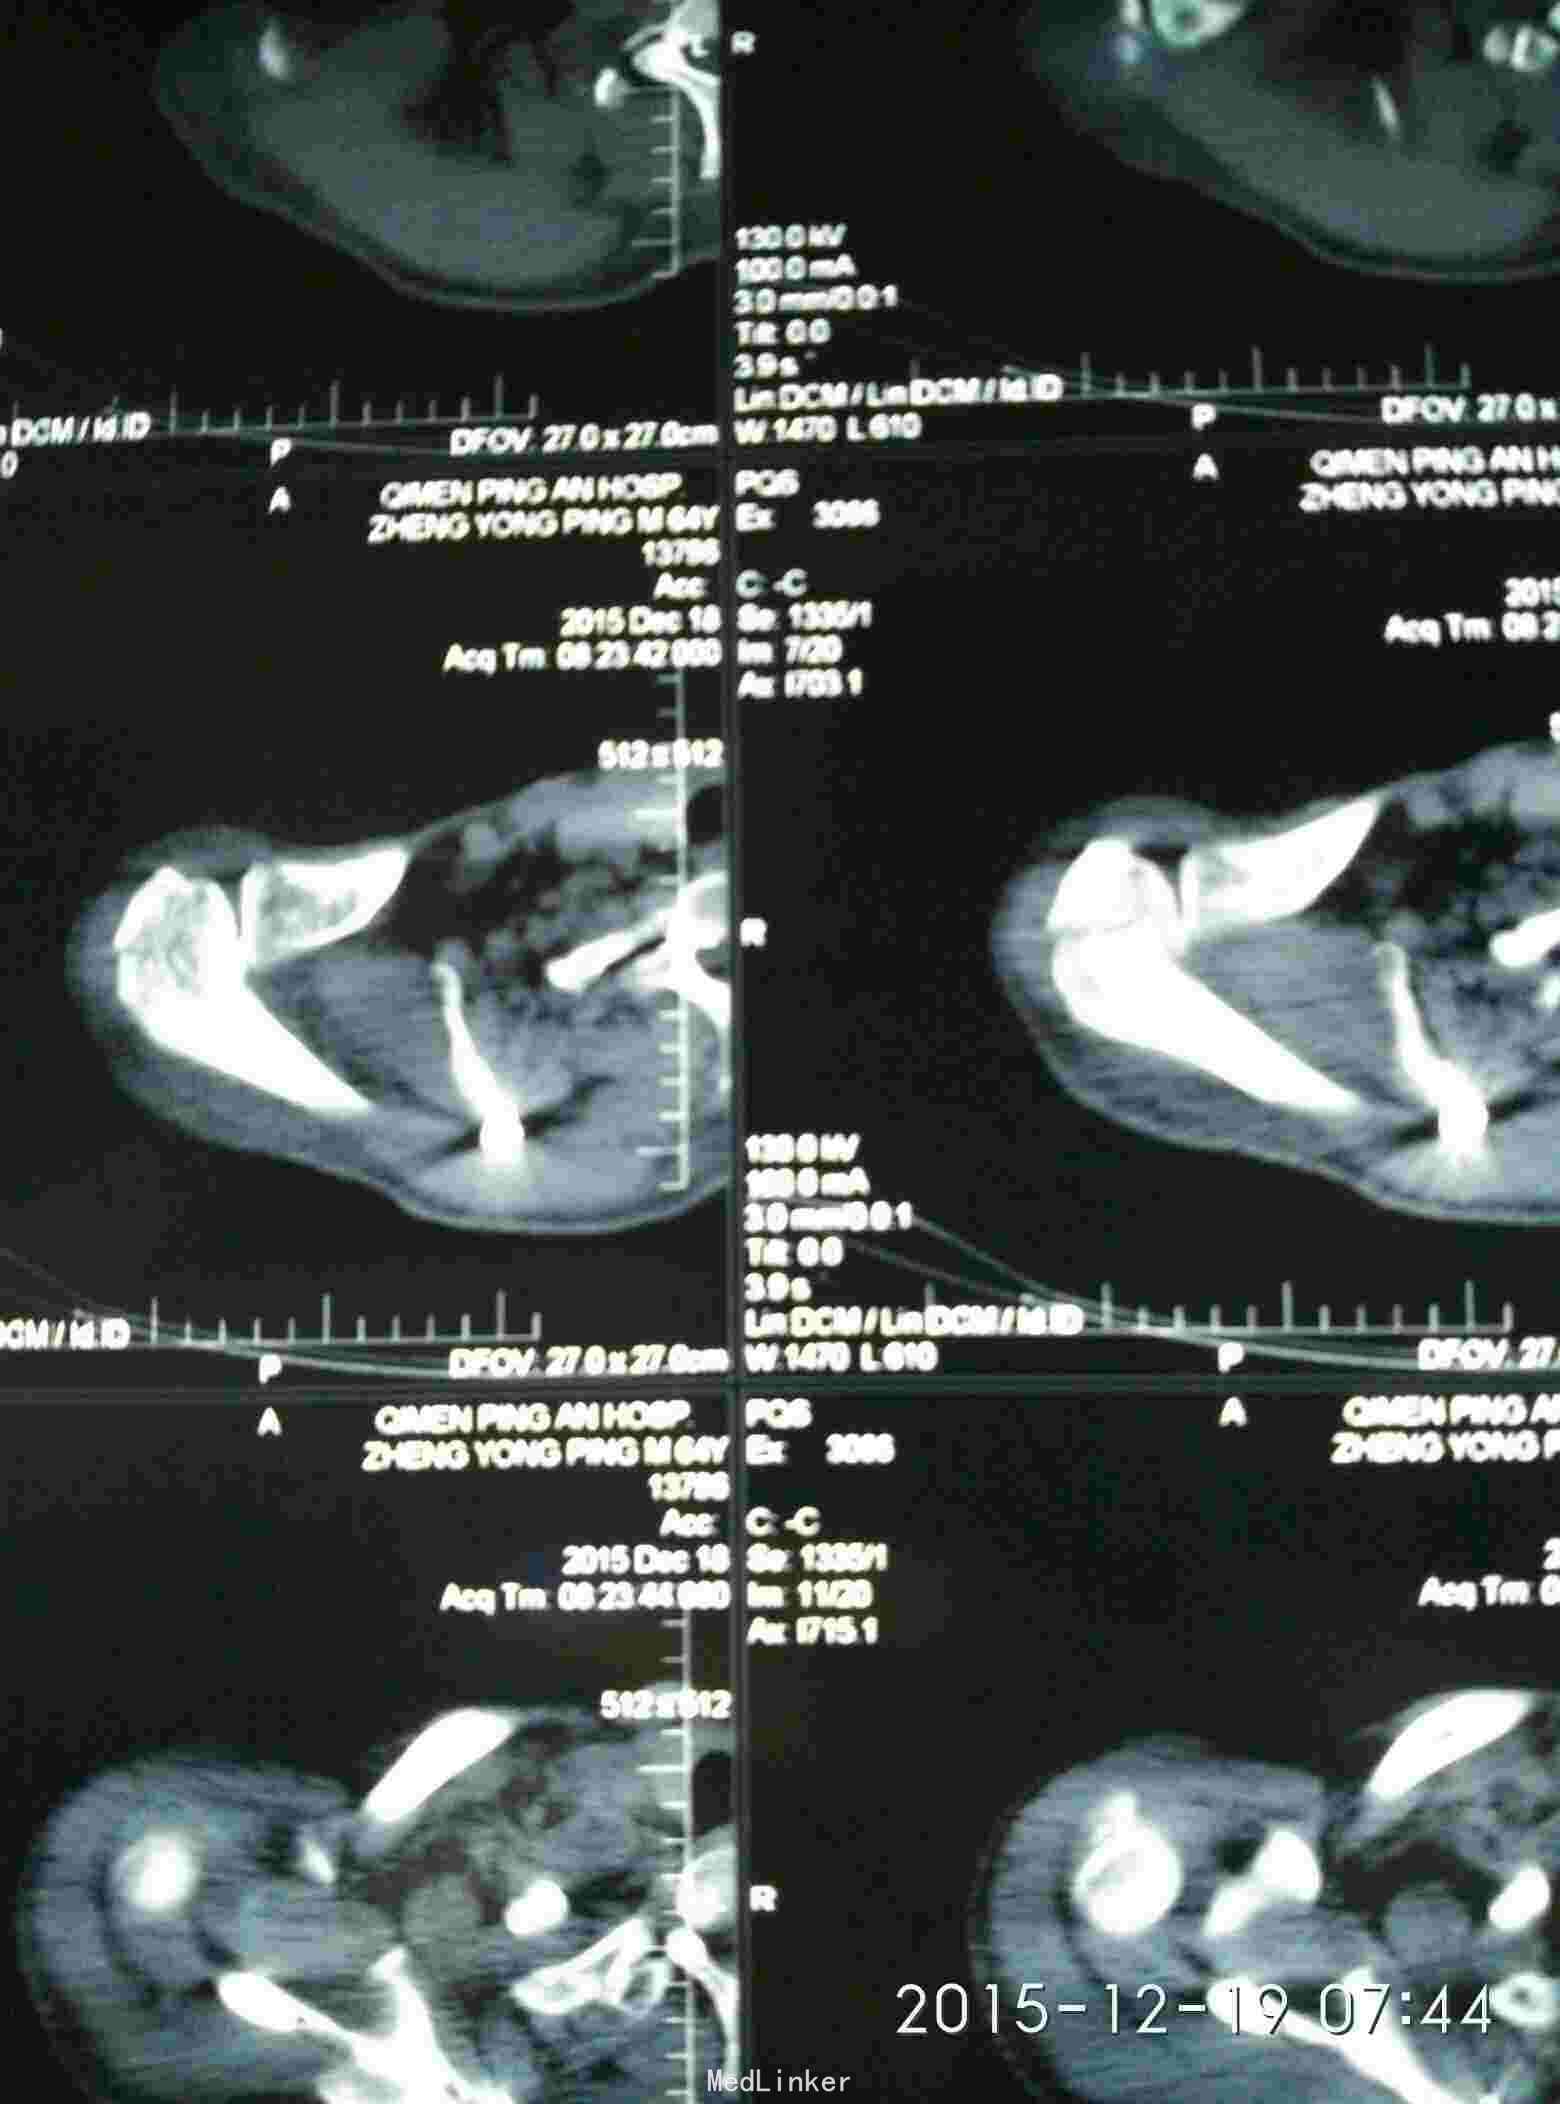

胸廓挤压试验阳性,右肩峰压痛阳性,右肩主动活动受限,外展约30度。x片及CT示右肩峰骨折及肩胛骨骨折,右第6.7.8.9肋骨骨折。

右肩峰骨折,右肩胛骨骨折,右第6.7.8.9肋骨骨折